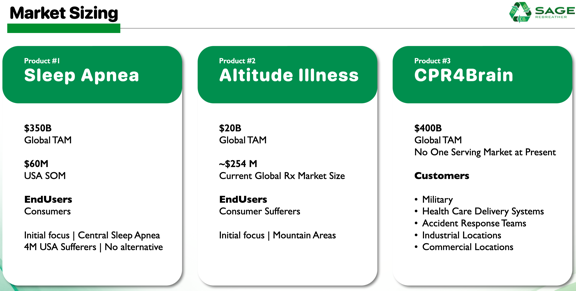

Sleep Apnea

Altitude Illness, and

Reversing Brain Injury

Our SAGE Rebreather opens the door for making life better for millions. Our platform technology appears to be able to overcome 15+ adverse human conditions measuring in excess of 2 billion people worldwide. Here are the numbers we've been able to find for just the first three use-cases...